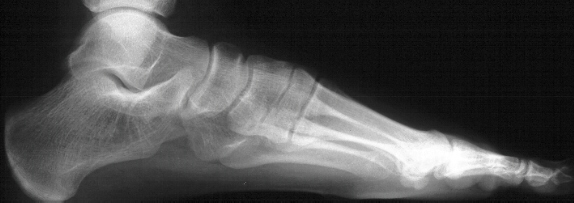

This a 13 year old white female complains of left foot pain. The pain has been present for approximately 2 years. There is no specific history of a traumatic event. The pain is primarily at the lateral aspect of the foot and is worse at the end of the day. The pain is somewhat relieved by rest. The left foot is without swelling. It is tender in the anterolateral aspect of the foot. Ankle motion is normal. Subtalar motion is significantly limited.

This is most likely a congenital deformity of the tarsal bones.